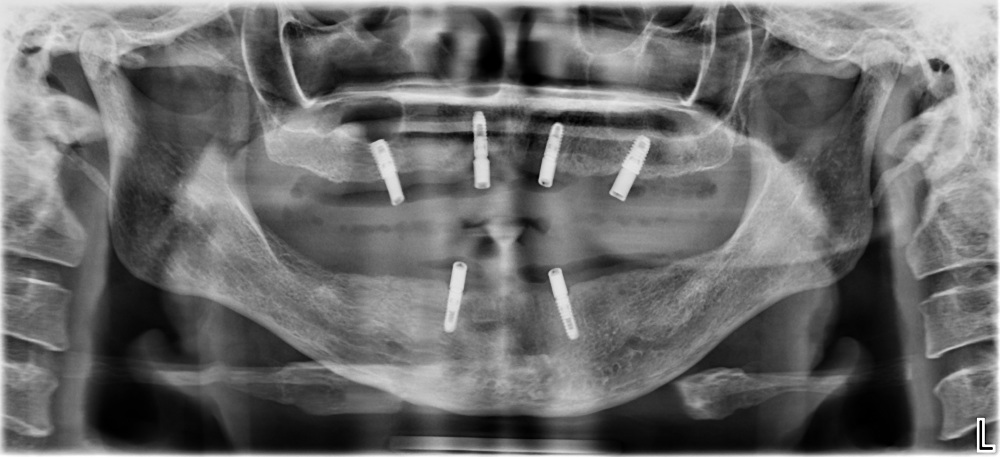

(All on 6)

Full mouth rehab

(Implant supported dentures)

Lower Jaw Rehab

Implant Placement using surgical guides for precision, the titanium implant is placed into your jawbone, typically 30-60 minutes with local anaesthesia.

A 3-6 month healing period for implant to integrate with bone (osseointegration). You’ll have a temporary solution during this time.